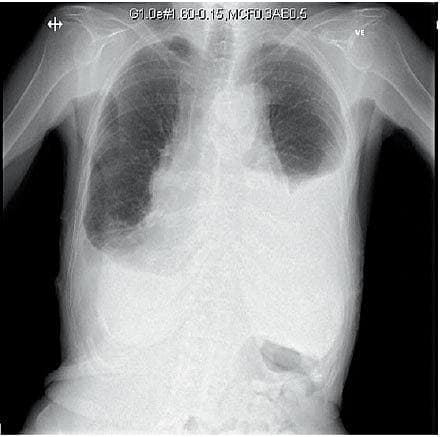

I den undersøgte periode blev der foretaget 29 pleuracenteser. Af disse var der i 14 (48,2%) tilfælde angivet en korrekt procedurekode, og i 15 (51,2%) tilfælde blev indgrebet fundet ved journalgennemgang. Der blev fundet ét tilfælde af pneumothorax og ingen andre komplikationer i relation til indgrebet. Dette giver en pneumothoraxrate på 3,4% (95% konfidens-interval 0,09-17,76%). I samme periode blev der udført 43 ascitesdrænager, hvoraf 33 (77%) havde en procedurekode, og de resterende 10 (23%) blev fundet ved journalgennemgang. Der blev observeret ét tilfælde (2,3%) af asciteslækage. Ingen tilfælde af sårinfektion eller blødning blev fundet ved journalgennemgang. Der var i perioden fire læger, der udførte ascitesdrænage, og to læger, der udførte pleuracentese.

I en nyere metaanalyse angives pneumothoraxraten efter pleuracentese at være 2,9% [4]. Der er ikke vist nogen signifikant ændret risiko ved udførelse af mindre rutineret personale versus af højtspecialiseret personale[4]. I vores materiale blev pleuracentesen udført af mindre rutineret personale. Vi fandt en risiko på 3,4%, men risikoen anses reelt for at være lavere pga. ufuldstændig registrering af ukomplicerede pleuracenteser; hyppigheden er desuagtet af samme størrelsesorden som den, der er fundet i andre studier, nemlig 2,9% [4].